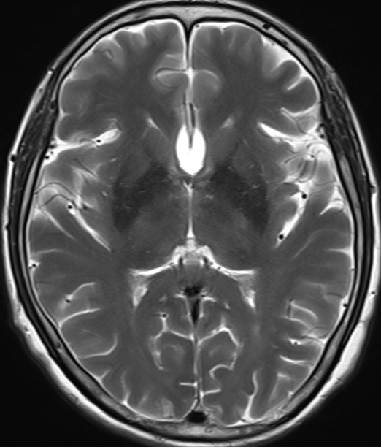

2013-8-2 MRI

2013-8-2 CT

腰穿脑压240